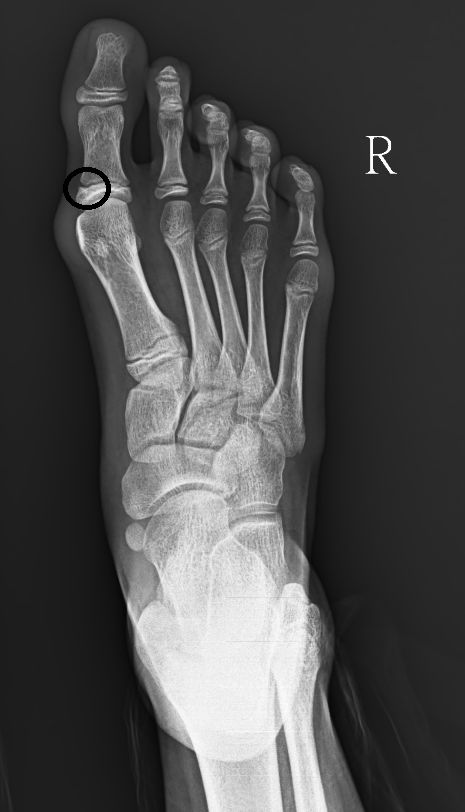

而小朋友發生大拇趾外翻的比率雖然沒有大人多,但依然有不少小朋友為此感到困擾,也會造成未來成年後的疼痛。因此我們可以趁小朋友進入青春期前,大約10歲左右時進行手術,其手術的方式與成年人的相較之下較為簡單。只需要將大拇趾內側一半的生長板破壞掉使其不在生長,(圖片 圓圈處)在外側生長板的生長下就能長出正常沒有外翻的大拇趾,手術不僅簡單也不需要鋼釘固定,疼

痛程度也相對小了很多。與其以後動大手術,不如趁尚未長大前,用簡單的手術解決,以免成人後再接受更大的痛苦。